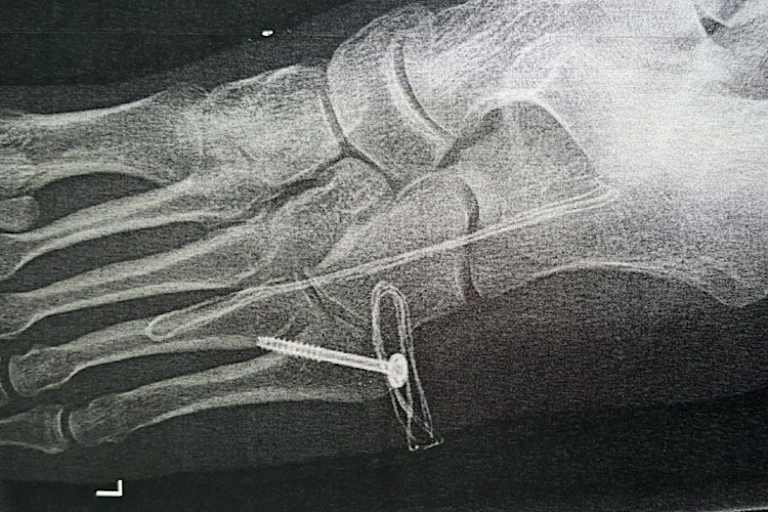

Nach einem verunglückten Sprung aus seinem Transporter, bei dem er sich einen Mittelfußknochen brach, ist die Saisonvorbereitung von Matti Seidel vorerst ins Stocken geraten.

"Der Bruch wurde inzwischen operiert und verschraubt", erklärt Matti Seidel, der die Saison 2015 auf dem sechsten Gesamtrang in der Superbike-Wertung der International Road Racing Championship beendete. "Obwohl ich im Augenblick den Fuß nicht belasten darf, hoffe ich, dass ich bald wieder mit dem leichten Training anfangen kann. Sobald es die Witterung zulässt, möchten wir auch auf der Strecke testen, um den neu überarbeiteten Motor einzufahren."